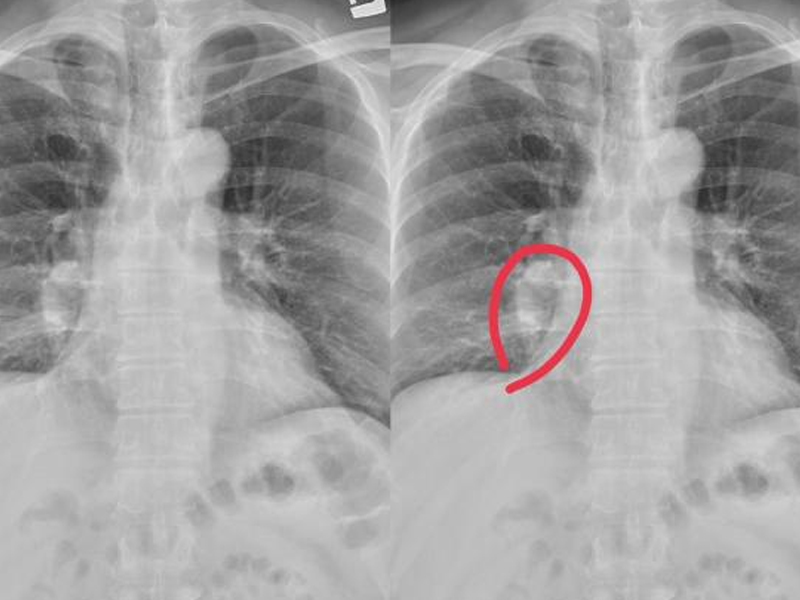

一說起女性陰唇變黑了變暗了,可能不少人首先想到的就是性生活太頻繁所致,甚至會得出此人生活不檢點的結論。真是這樣嗎? 民間素有性生活頻繁會使女性的外生殖器變黑的傳言,甚至以大陰唇表皮的色素沉著程度來判別是否處女,這是極不可信的。通常,大陰唇的顏色從褐色到淺黑色不等,範圍與陰毛髮生部位一致。雖說生過孩子和有過性生活的婦女,有色素沉著範圍擴大、越過陰毛髮生部位使顏色變深的傾向,但是,這也只能說明性生活頻繁是私處變黑的原因之一,但並不是唯一原因。就是十幾歲的處女也有大面積色素沉著的例子。所以,用大面積色素沉著來判斷對方有否濫交,是極不可取的。 陰唇發黑的 6 大原因 原因 1:荷爾蒙變化 不少地方的專業資料上都提到了女性私處變黑的一個原因“荷爾蒙分泌紊亂”。原來,女性私處的顏色是受本身黑色素沉澱的影響,而這種色素沉澱與女性荷爾蒙分泌密切關係。女性從幼年時期,陰部尚未發育,所以整個外生殖器是被大陰唇蓋住的,陰部皮膚與其他部位的皮膚顏色相同。 但到了女性發育期後,受荷爾蒙的影響,女性會陰部會長毛,並且小陰唇也會較突出於大陰唇,此時的陰部顏色也會開始加深。特別是懷孕後,荷爾蒙的改變造成陰唇變黑,即使產後恢復較好,因為荷爾蒙的改變也不可能恢復到產前的樣子 原因 2:氣鬱悶結 還有一個比較重要的原因就是心情了。為什麼這麼說呢?因為女人本身有經,帶,胎,產等特殊生理過程,日常生活中負擔又重,肩負工作和家庭的雙重壓力,所以往往比其他人群更容易受到風,寒,署,熱等外邪侵害,導致氣機失調,內分泌紊亂,黑色素不易及時排出體外。加上女人比較敏感,情緒不是很穩定,思慮過度等乾擾身體內部氣血運行,更容易引起黑色素沉積,從而導致陰唇變黑。所以,保持愉悅的心情對私處美白也很重要,切不可忽視。 原因 3:房事過度 房事也是影響私處變黑的一個常見原因。因為性生活時,陰唇長期反复受到外來摩擦的刺激,以致局部色素沉著增加,其色澤就會隨時間的遷移而日見加深,女人私密部位色澤越來越暗沉。因此,女性朋友在房事生活上要合理控制,不要過度,每週房事次數在3次以下為宜,以免影響私處顏色變化。 原因 4:行為習慣 由於工作需要或是個人習慣,有些女性私處長期處於摩擦狀態,包括走路產生的摩擦,都會產生大量皮膚黑色素沉澱,久而久之導致私處顏色變黑。為了防止私處變黑,女性朋友們盡量少穿牛仔褲之類的緊身褲,以減少私處摩擦。平時走路時,也少穿高跟鞋,避免腿部走路過度用力摩擦私處。 原因 5:亂用護理產品 總有一些女性朋友喜歡跟著感覺走,常常憑著自己的判斷和經驗,自作主張選擇使用私處護理產品。由於某些產品添加的違禁成分,或是某些化學物質的影響,往往會產生一定的腐蝕性,導致私處部位的黑色素沉積加快進而變黑變暗。專家提醒廣大女性朋友,選擇私處護理產品時請務必慎重。 原因 6:遺傳 遺傳因素也是陰唇變黑的一個原因,雖然並不常見,但個別女性也會因為母親或者外祖母的遺傳因素,導致私密部位變黑。 目前,市場上的私處美白產品很多,比較常見的有天然修復液、色素、酵素晶體、中藥等。處於安全性方面的考慮,動植物提取物質為主要成分的私處美白產品更受歡迎。當然,還要注意產品的 PH 值大小,鹼性的產品會破壞私處健康環境,容易導致婦科疾病,專家提醒不宜長期使用鹼性的私處美白產品。 |